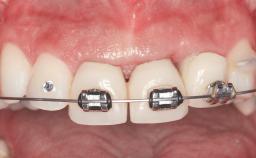

Replacement of Four Incisors with a Fixed Partial Denture on Two Narrow-Neck Implants after Implant Failure

| Area | Anterior |

| Patient's Esthetic Expectations | Low | Medium | High |

| Esthetic Risk | High |